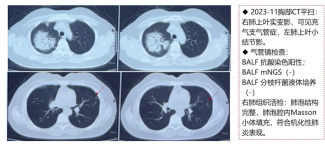

3.胸部CT

1)2023年11月(首次发病):右肺上叶实变影,左肺上叶多发小结节影。

2)2023年12月(激素治疗2个月后):右肺上叶实变影明显吸收,左肺上叶阴影仍存在。

4.病理检查

2023年11月右肺组织活检:肺泡腔内马松小体填充,符合机化性肺炎表现。